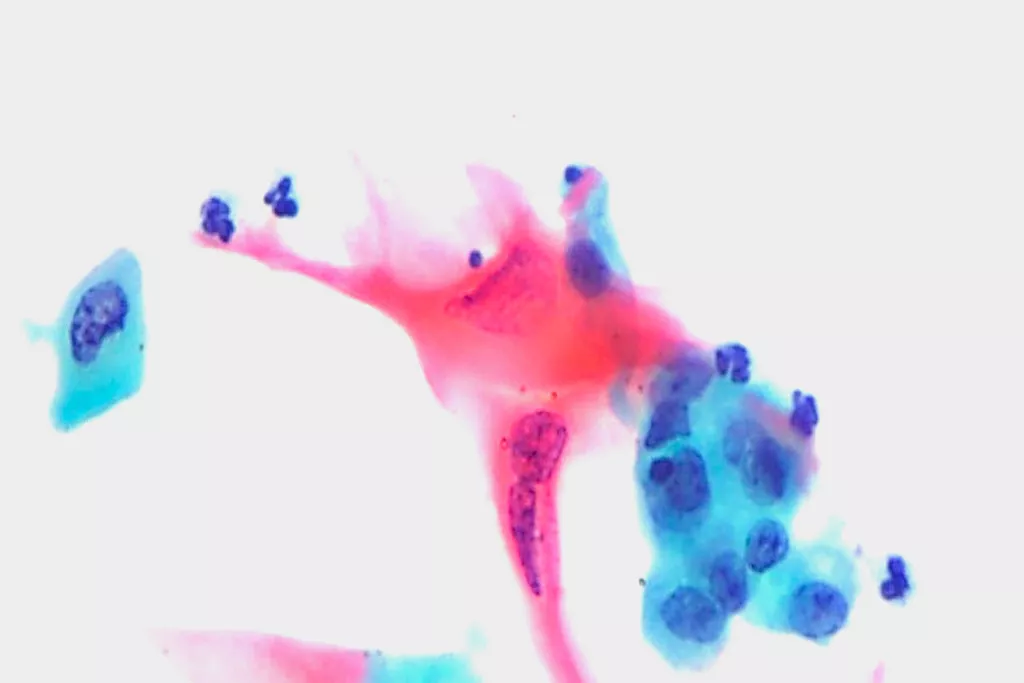

Galería de imágenes9

9. Imagen enviada por el Dpto. de Citopatología del Hospital de Llandough, Gales.